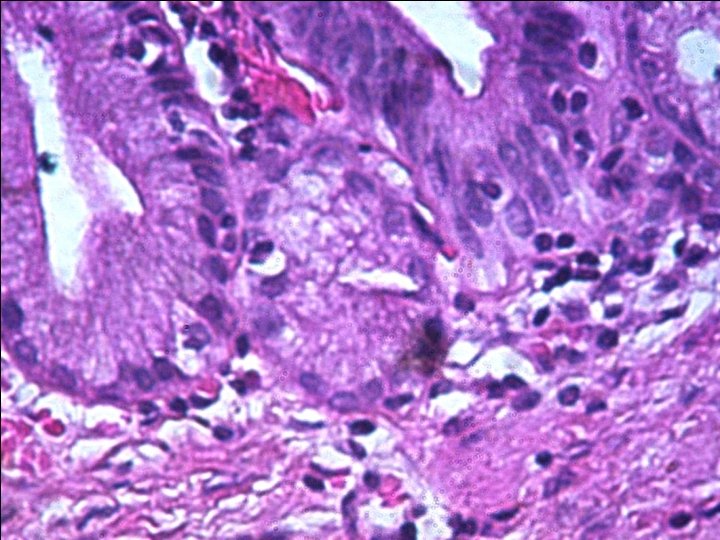

Pathology § Microscopic Description: Sections show fibrotic cyst wall with columnar epithelial lining, inflammation and ulceration area. § Diagnosis: Choledocal cyst wall, resection: - Cyst wall with fibrosis, hemorrhage, acute & chronic inflammation and ulceration.

§ Pathologic features of choledochal cysts are variable, ranging from normal bile duct mucosa to carcinoma. § More commonly in children there is a densely fibrotic cyst wall with evidence of chronic and acute inflammation. § In adults, there are frequently inflammatory changes, erosions, sparse distribution of mucin glands, and not infrequently metaplasia.